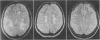

OBJECTIVE--To compare the abnormalities shown by magnetic resonance imaging of the brain in three clinically distinct groups of patients with multiple sclerosis, and to correlate the extent of abnormality with the degree of clinical disability in the three groups. DESIGN--All patients underwent magnetic resonance imaging and full neurological examination, and their disability was scored according to the expanded Kurtzke disability state scale. SETTING--National Hospital for Nervous Diseases (Multiple Sclerosis NMR Research Group). PATIENTS--Three groups of patients with confirmed multiple sclerosis were studied: 12 patients with minimal disability despite a long (greater than 10 years) duration of illness (benign multiple sclerosis), 16 who had developed progressive disability after a relapsing and remitting course (secondary progressive multiple sclerosis), and 13 who had had progressive disability from the onset of the disease (primary progressive multiple sclerosis). MAIN OUTCOME MEASURES--Number and size of lesions in 17 anatomically defined sites; total lesion load, estimated with an arbitrary scoring system weighted for the size of lesions; and disability score. RESULTS--Magnetic resonance imaging showed that all 41 patients had abnormalities. These were extensive in the groups with secondary progressive and benign disease compared with the group with primary progressive disease. The lesions in the patients with secondary progressive disease were larger and more confluent than those in the two other groups (p = 0.007). Most lesions (85%) in the patients with primary progressive disease were under 5 mm in diameter; this percentage was higher than that in the two other groups (p = 0.032). Consequently the patients with primary progressive disease had the lowest mean lesion load (36.7); that in the patients with benign disease was 52.7 and that in the patients with secondary progressive disease 64.6 (p = 0.05). No correlation existed between disability and total lesion load. The distribution of brain lesions and of detectable lesions of the spinal cord, and the frequency of cortical atrophy, were similar in all groups. CONCLUSIONS--No relation was found between the degree of clinical disability and the extent of abnormality shown by magnetic resonance imaging: patients with clinically benign disease often had extensive abnormalities and those with primary progressive disease had surprisingly few lesions. Though magnetic resonance imaging increases knowledge of the disease process in multiple sclerosis and is invaluable in diagnosis, it is not helpful in predicting disability in individual patients.

Images in this article